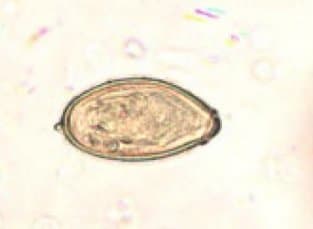

اغلب از تخمهای کلونورکیس سایننسیس غیرقابل تشخیص است. تخمها دارای اوپرکول هستند و اوپرکول دارای یقههای آشکاری است. تخمها هنگام دفع از طریق مدفوع جنیندار شدهاند.

Range 10-20*19-30 µm (average: 30*12 µm)